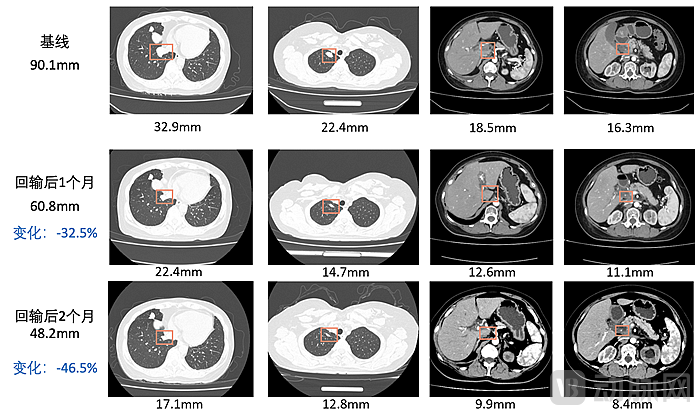

目前,呈源生物已经完成了合成型TIL的技术开发和可行性验证,并且建立了数条针对实体瘤的合成型TIL治疗管线。其核心管线已在IIT中完成了多例实体瘤患者的治疗。安全性、药代动力学等数据都展示了合成型TIL的优势,研究人员还在多个病人中观察到了肿瘤缩小。有一例病人的CT结果显示其肿瘤直径之和缩小了46.5%,并且达到确认部分缓解(confirmed partial response, cPR)的标准。下一步,呈源生物将积极申报IND,在注册临床中证明该疗法的安全性、有效性。

回输后患者肿瘤直径缩小46.5%,图源呈源生物